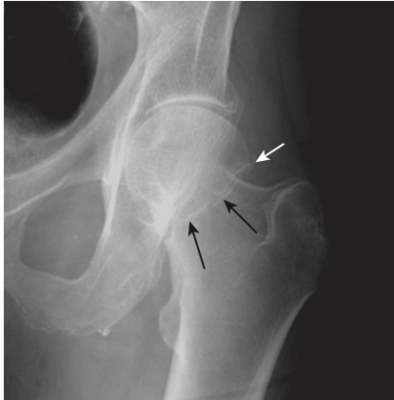

Gãy cổ xương đùi ở người già

- Thường gặp và thường liên quan đến loãng xương

- Chụp X quang cổ xương đùi thường quy nên được thực hiện với chân của bệnh nhân ở tư thế xoay trong để hiển thị cổ ở dạng trực diện. Tìm dấu gập góc của vỏ xương hoặc các vùng có tăng đậm độ chứng tỏ có sự chồng lấn (Hình 19).

- Đôi khi gãy cổ xương đùi có thể rất khó nhận biết và cần phải chụp MRI hoặc scan xương bằng phóng xạ hạt nhân để chẩn đoán.